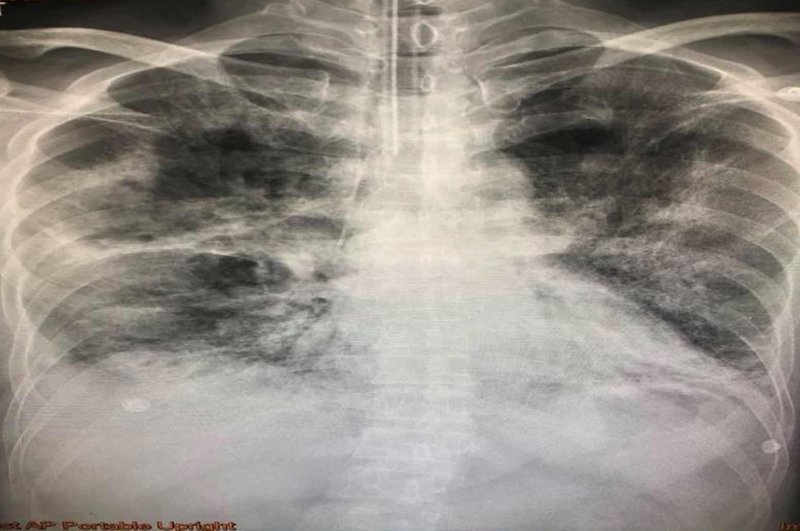

Thai man dies of fungus in the lungs - complications from the 'flu'

Picture: Daily News

A Thai doctor went online to share pictures and details of what happened to a 57 year old man who caught Type A Influenza.

Dr Manoon Leechawengwong said on Facebook that a previously healthy man caught the 'flu after visiting a friend for several days in a row in hospital.

Treatment was started with "Tamiflu" - a common treatment for Type A and B 'flu symptoms.

His condition first improved then got progressively worse. He was admitted to hospital and died 30 days later.

While his immune system was compromised he was infected with "Aspergillus Fumigatus" a fungus that attacks the lungs.

He was a half pack a day cigarette smoker.